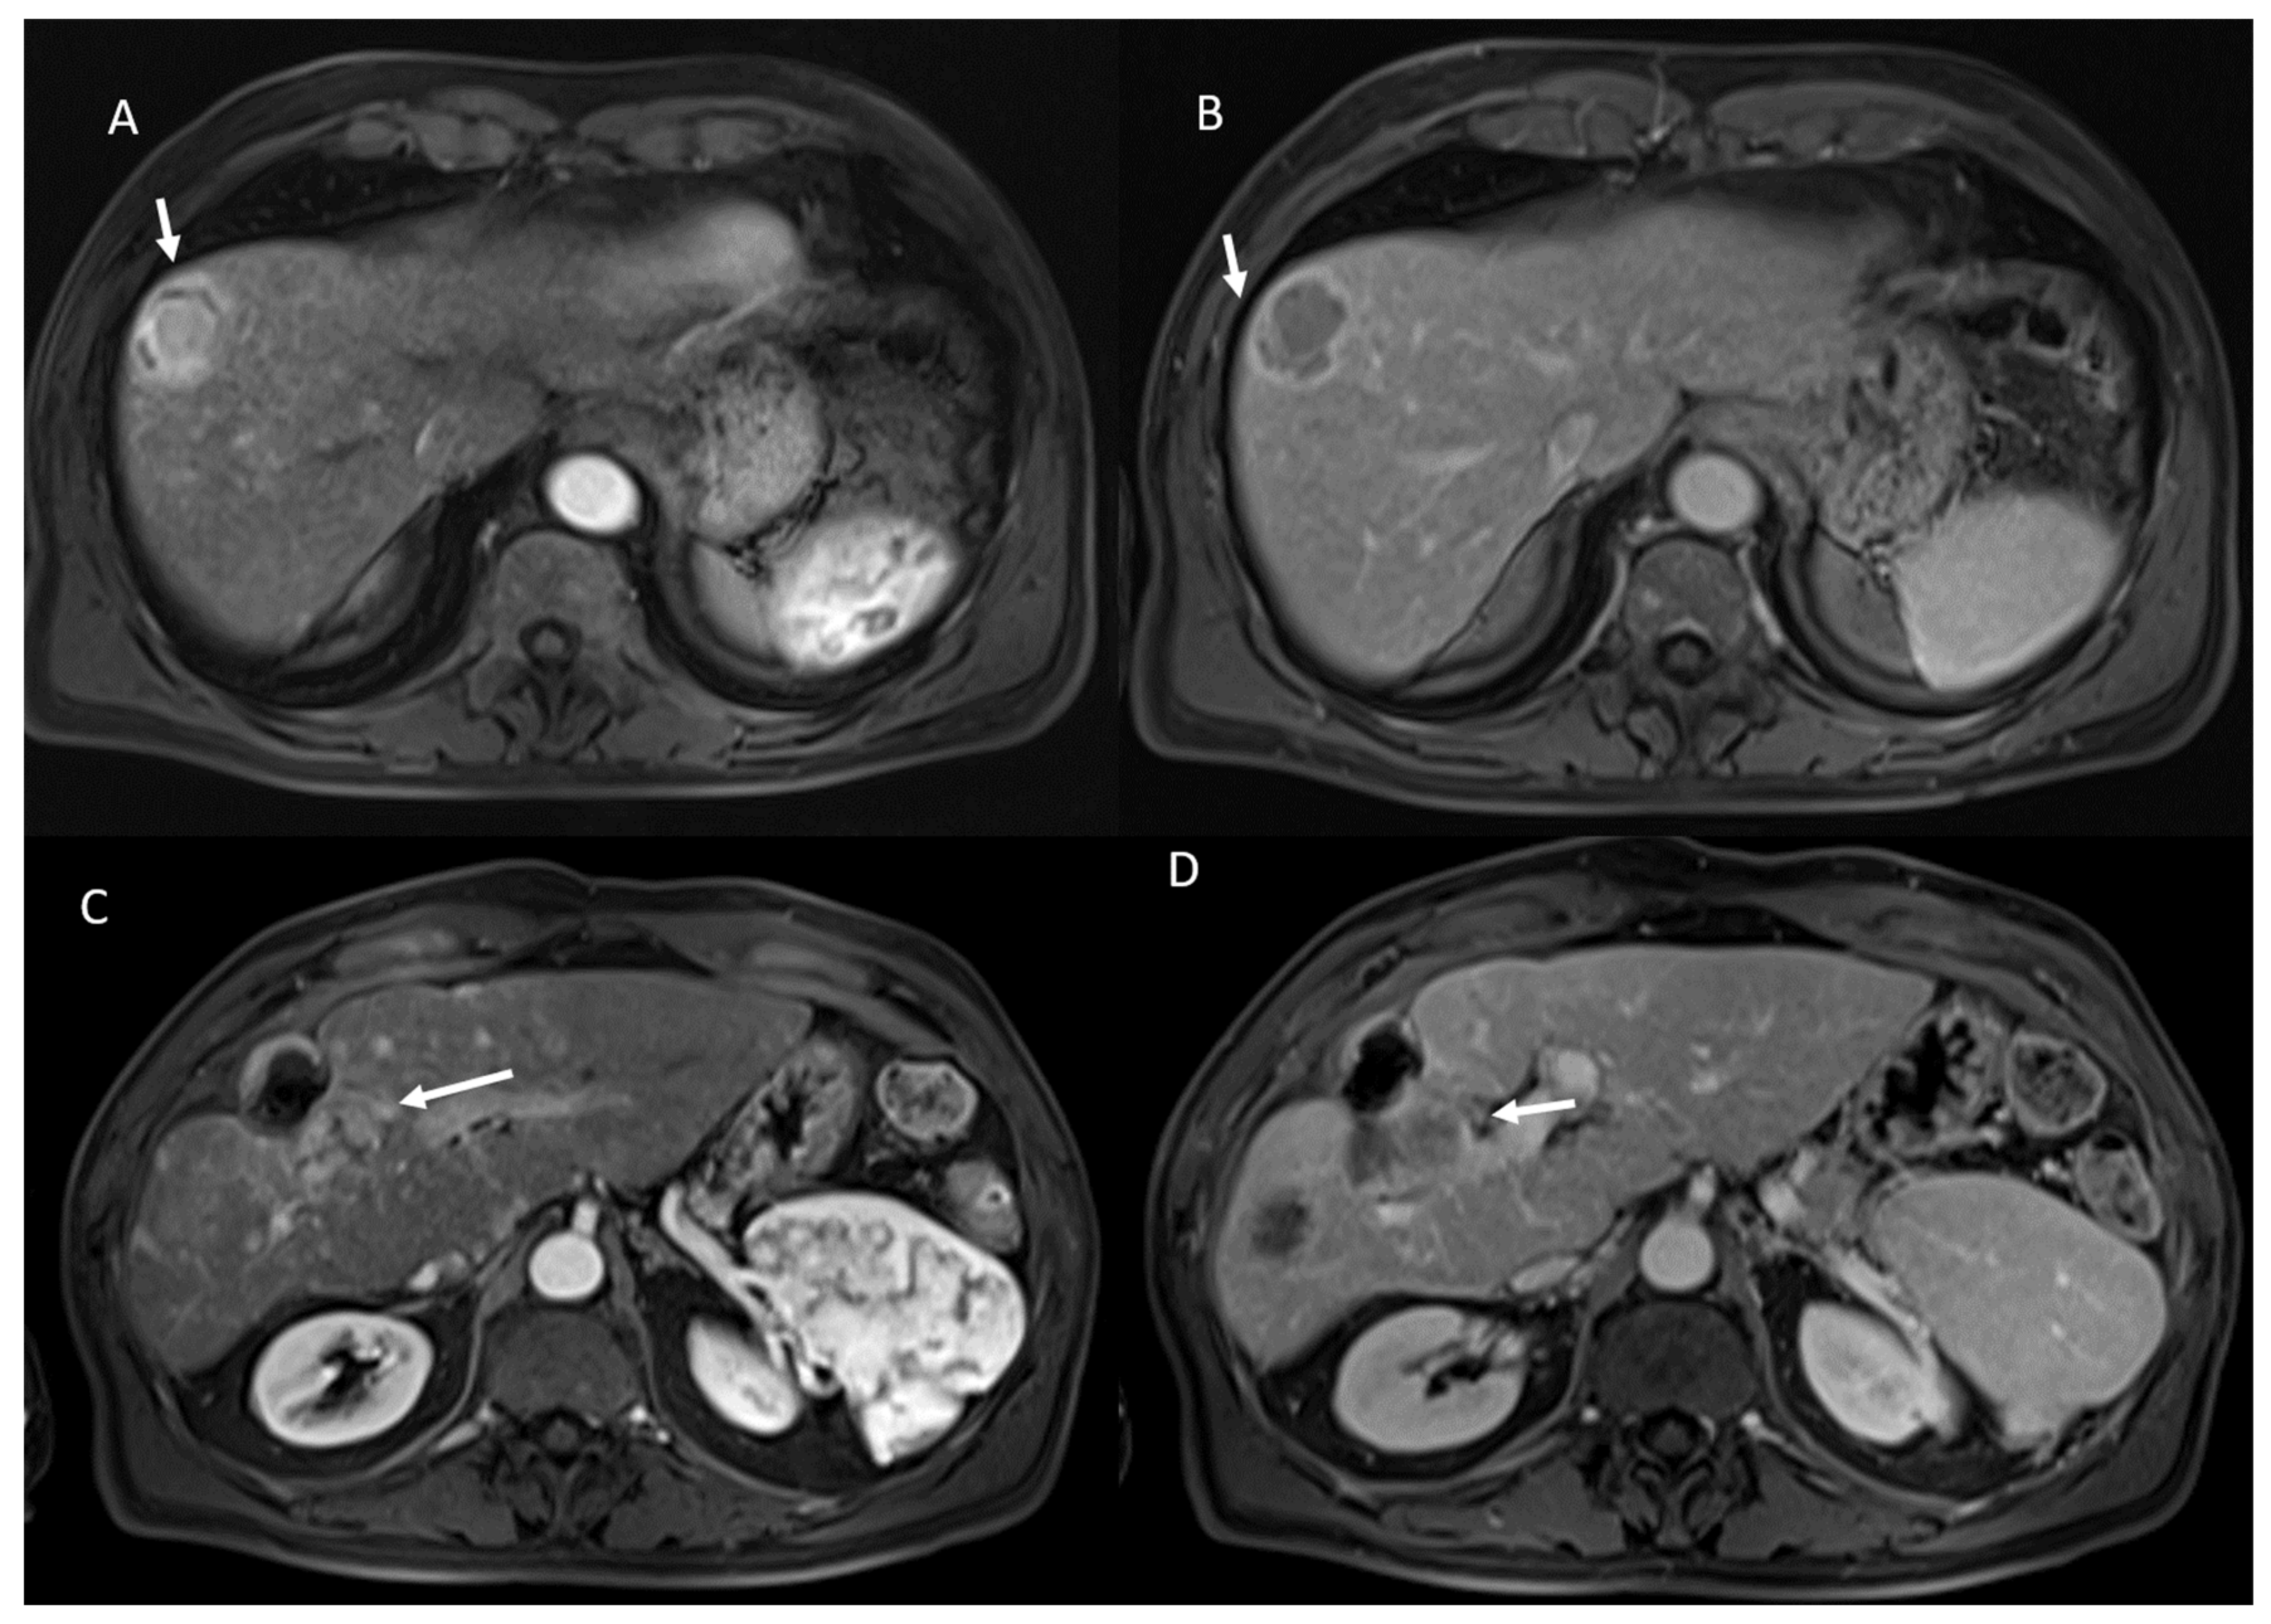

- 21 showed APHE and 2 rim APHE during arterial Phase (Figure 2).

- 23 showed wash-out appearance during portal phase and hypointense SI in equilibrium phase (Figure 2).

- 53 showed non rim APHE and 60 hypointense SI during arterial phase (Figure 5).

- 3 showed peripheral washout appearance and 110 hypointense SI in portal phase (Figure 5).

- 113 lesions were hypointense in equilibrium phase.